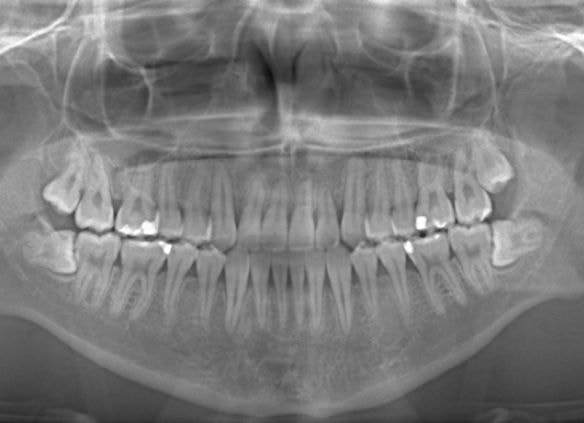

やはり統計通り、左上3番の埋伏です。

左上2番の歯根吸収が認められますが、保存不可能なレベルではありません。

成人の反対咬合なので、少し顎関節にダメージはありますが、重症ではありません。

治療中のレントゲンです。

7番、8番の状態や歯根のパラレリング(平行性)をチェックしています。

左上2番の歯根の状態もなんとかもちそうです。

上顎劣成長症例ですが、鼻腔の状態も悪くありません。